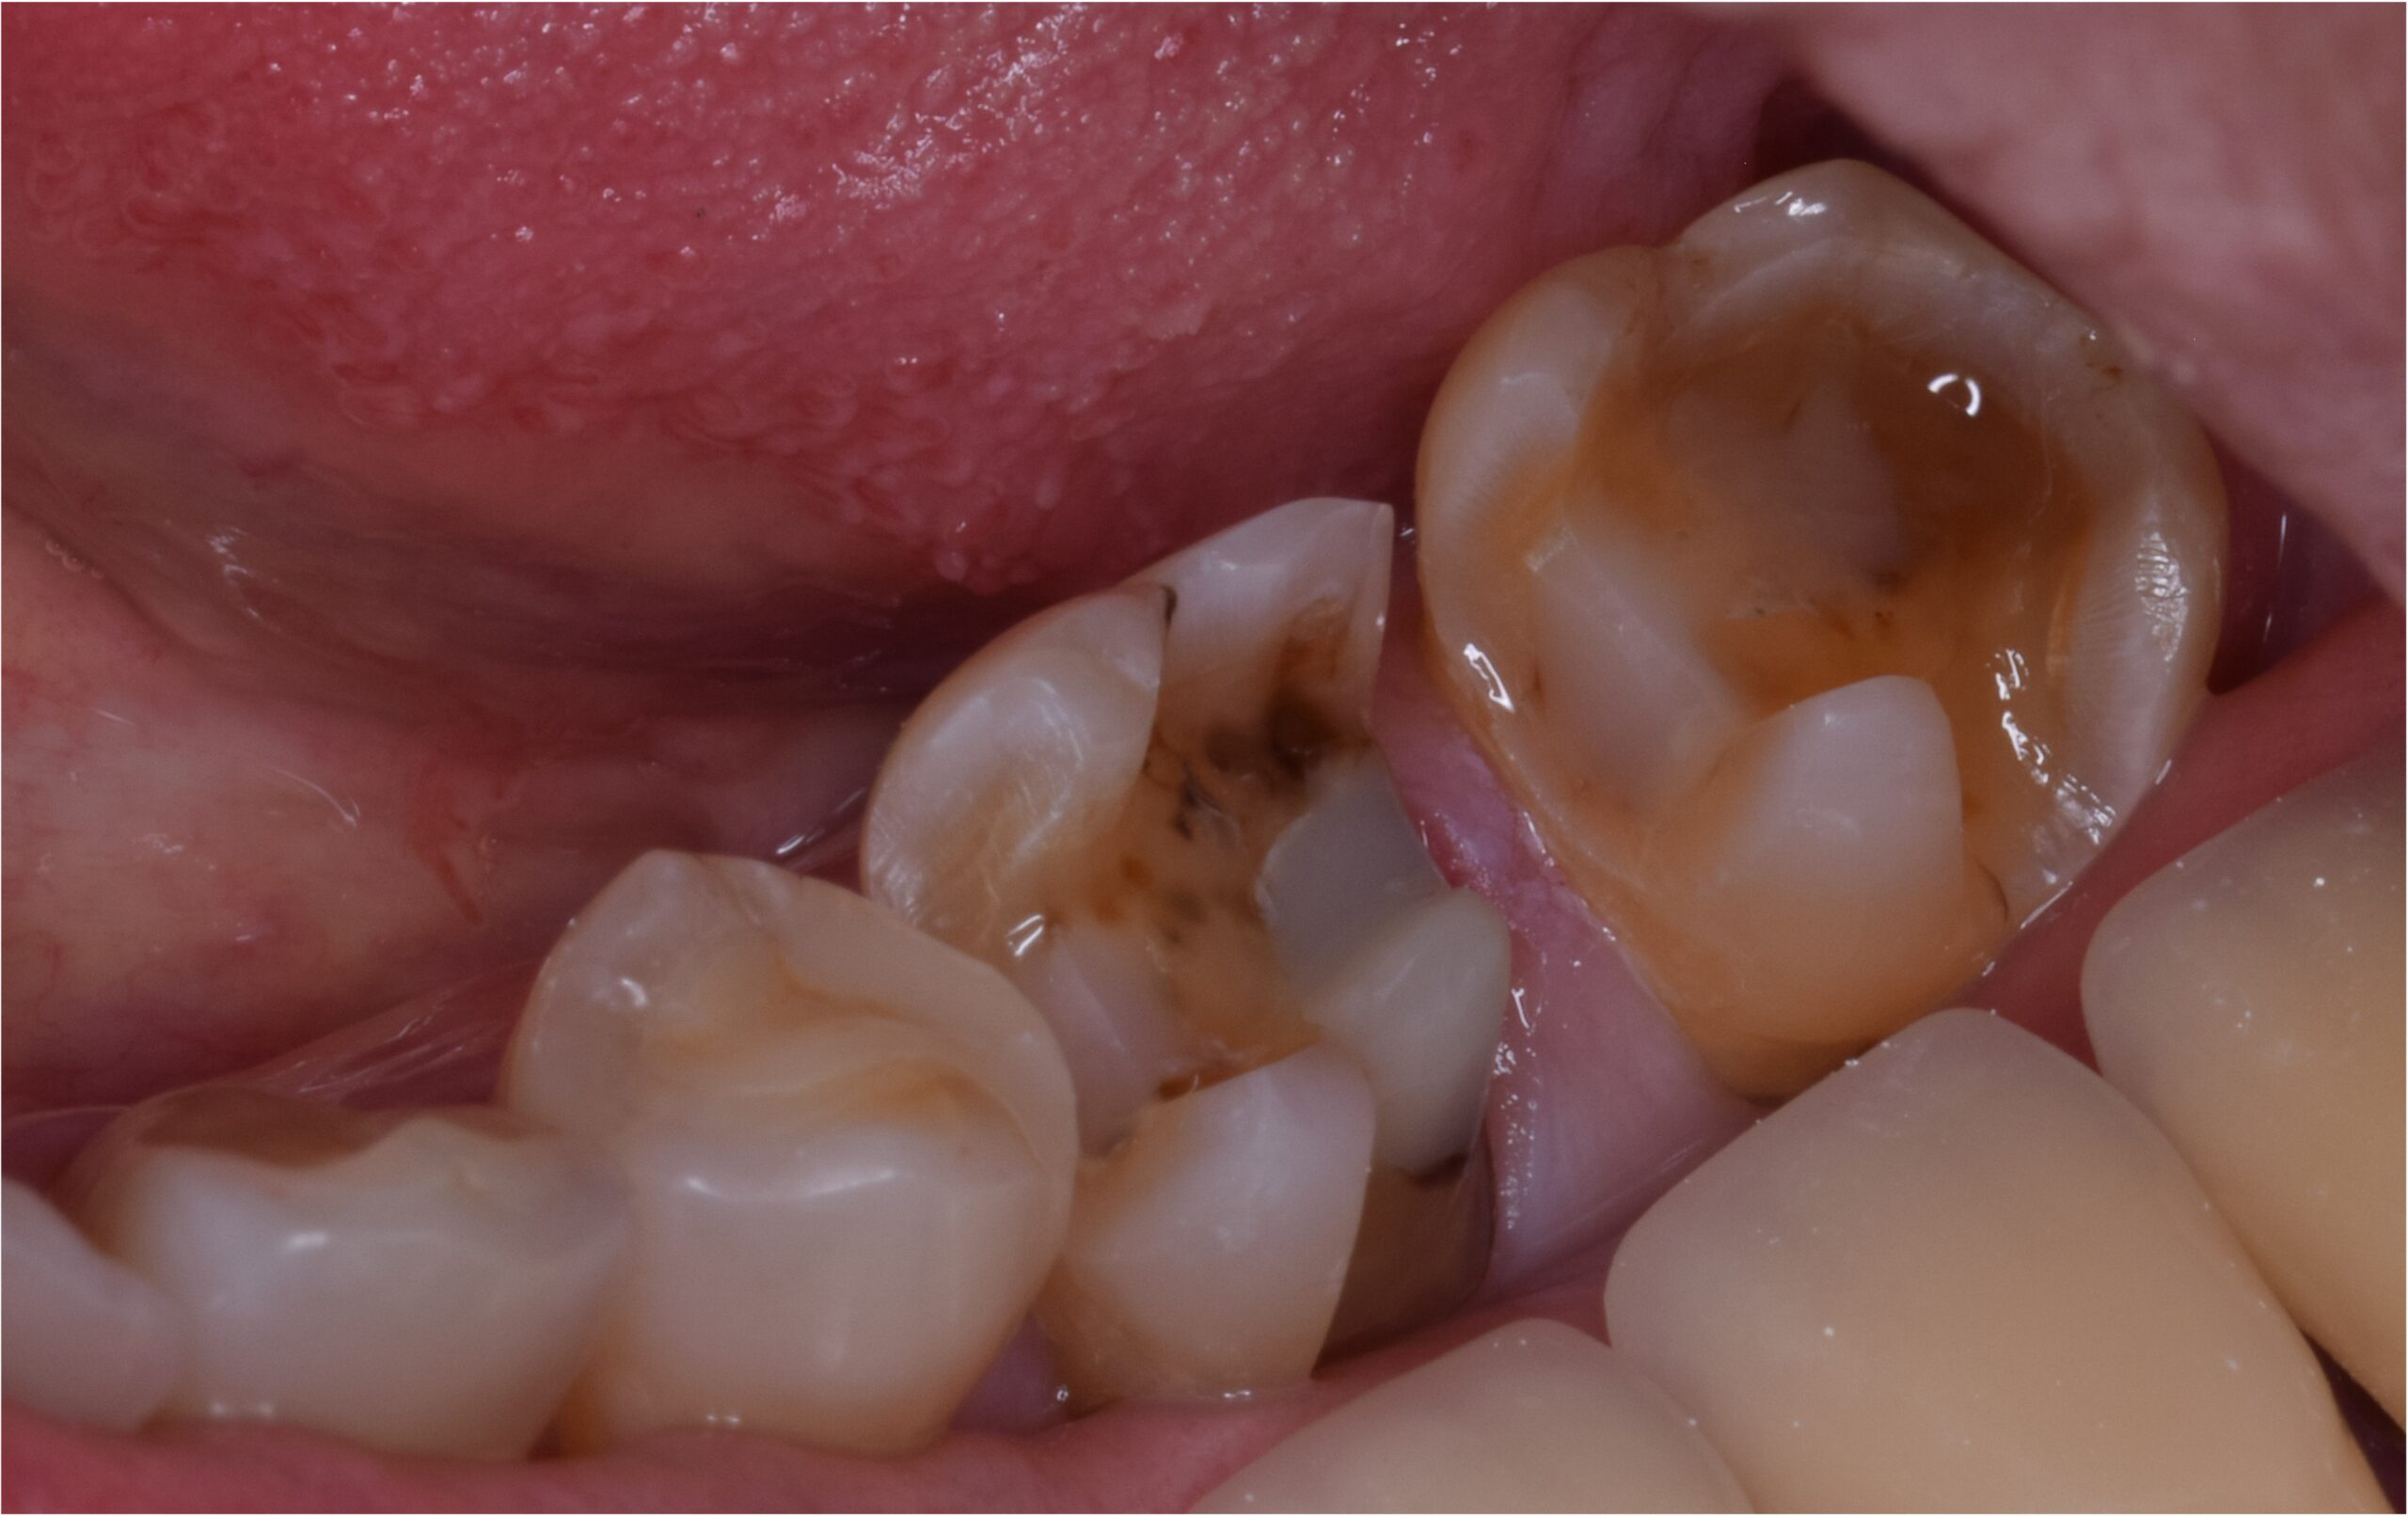

| 主訴 | 検診してほしい 銀歯の下が虫歯になっていたため治療 |

| 治療内容 | 虫歯治療、セラミックブリッジ治療 |